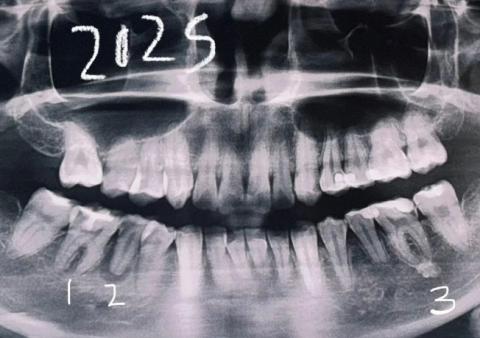

Dental Case Analysis – Full Mouth Panoramic X-Ray With Multiple Infection Sites

This panoramic dental X-ray shows a full-mouth view of the maxilla and mandible. Several teeth demonstrate radiographic signs of infection, bone loss, and previous dental treatment. The findings suggest chronic, multi-site dental pathology rather than a single isolated issue.

General Radiographic Findings

Multiple teeth with widened periodontal ligament spaces

Areas of reduced bone density around root apices

Irregular alveolar bone levels

Signs consistent with chronic inflammation

Mixed dental history including untreated, treated, and compromised teeth

Upper Jaw Findings

Possible apical radiolucencies on posterior teeth

Early to moderate bone loss

Sinus floor appears intact but close to root apices

Risk of sinus involvement if infections progress

Lower Jaw Findings

Noticeable bone loss around posterior molars

Possible chronic apical infections

Increased risk to mandibular nerve if lesions enlarge

Structural bone thinning in affected areas

Diagnosis

Chronic apical periodontitis affecting multiple teeth

Generalized dental infection with localized bone loss

Long-standing inflammatory dental condition

Panoramic X-rays often reveal hidden, silent infections that are not yet symptomatic. Early intervention and staged treatment planning are critical to preserve remaining bone and teeth. Full-mouth cases require coordinated, long-term care.